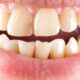

Odbudowa zęba na włóknie szklanym – zalety i przeciwwskazania

Odbudowa zęba na włóknie szklanym to popularny sposób zakończenia leczenia endodontycznego (kanałowego). Zabieg…